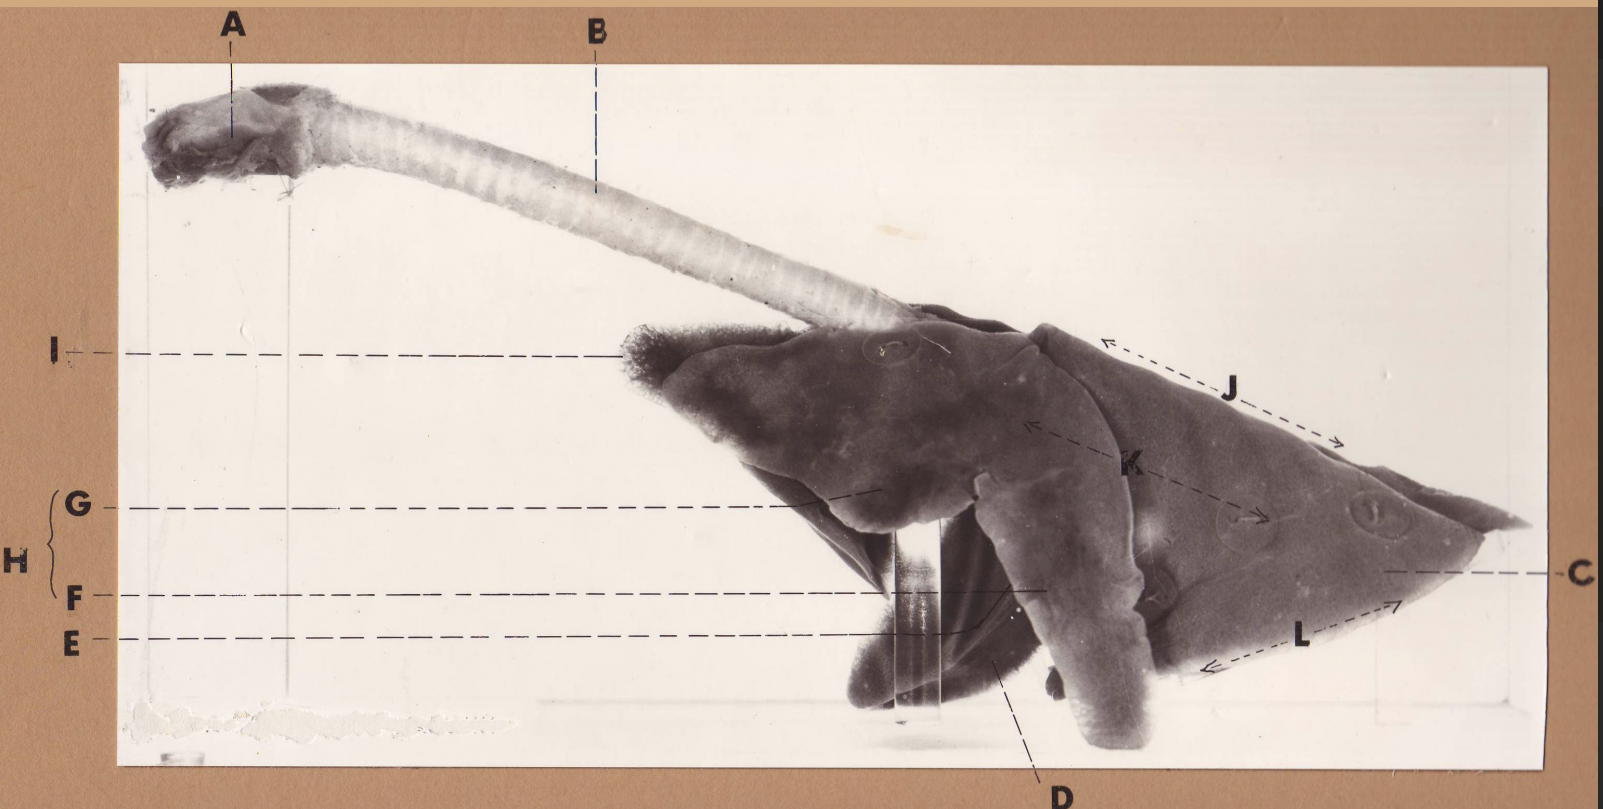

A

(cat larynx/trachea/lungs, L lateral)

larynx

B

(cat larynx/trachea/lungs, L lateral)

trachea

C

(cat larynx/trachea/lungs, L lateral)

caudal lobe

D

(cat larynx/trachea/lungs, L lateral)

middle lobe

E

(cat larynx/trachea/lungs, L lateral)

cardiac notch

F

(cat larynx/trachea/lungs, L lateral)

caudal segment

G

(cat larynx/trachea/lungs, L lateral)

cranial segment

H

(cat larynx/trachea/lungs, L lateral)

cranial lobe

I

(cat larynx/trachea/lungs, L lateral)

apex

J

(cat larynx/trachea/lungs, L lateral)

dorsal border

K

(cat larynx/trachea/lungs, L lateral)

costal surface

L

(cat larynx/trachea/lungs, L lateral)

basal border